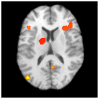

A growing number of studies examine instructional training and brain activity. The purpose of this paper is to review the literature regarding neuroimaging of reading intervention, with a particular focus on reading difficulties (RD). To locate relevant studies, searches of peer-reviewed literature were conducted using electronic databases to search for studies from the imaging modalities of fMRI and MEG (including MSI) that explored reading intervention. Of the 96 identified studies, 22 met the inclusion criteria for descriptive analysis. A subset of these (8 fMRI experiments with post-intervention data) was subjected to activation likelihood estimate (ALE) meta-analysis to investigate differences in functional activation following reading intervention. Findings from the literature review suggest differences in functional activation of numerous brain regions associated with reading intervention, including bilateral inferior frontal, superior temporal, middle temporal, middle frontal, superior frontal, and postcentral gyri, as well as bilateral occipital cortex, inferior parietal lobules, thalami, and insulae. Findings from the meta-analysis indicate change in functional activation following reading intervention in the left thalamus, right insula/inferior frontal, left inferior frontal, right posterior cingulate, and left middle occipital gyri. Though these findings should be interpreted with caution due to the small number of studies and the disparate methodologies used, this paper is an effort to synthesize across studies and to guide future exploration of neuroimaging and reading intervention.